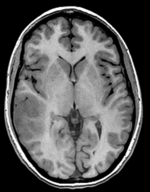

this is the fixed reference image. All images are aligned into this space lleft this is the T2 reference image, serves as target to the DTI baseline, but is itself aligned to the SPGR lleft this is the DTI Baseline scan, to be registered with the T2 this is the DTI tensor image, in the same orientation as the DTI Baseline

Registered DTI superimposed on SPGR and T2 registered (cycles show T1 and T2 and color DTI overlay)